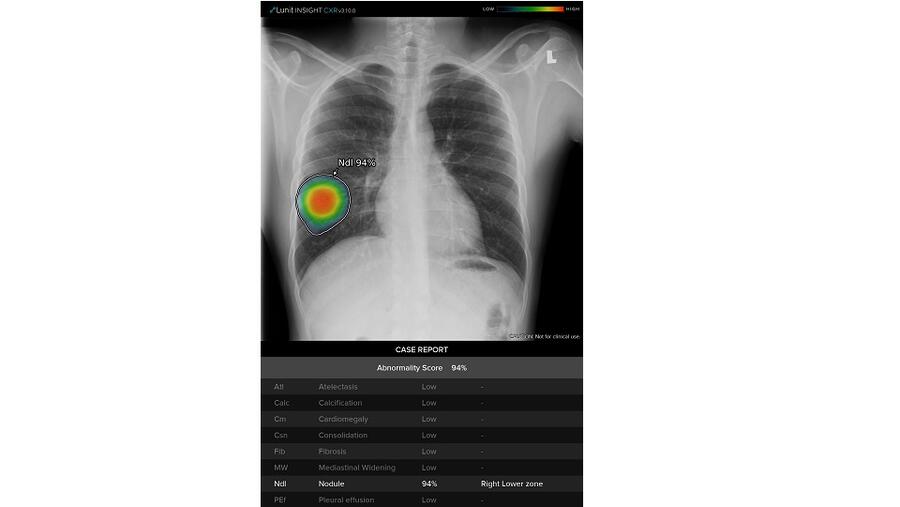

جنرال إلكتريك للرعاية الصحية تطلق منظومة جديدة مدعومة بالذكاء الاصطناعي لرصد النتائج غير الطبيعية في الصور الشعاعية بضائع وخدمات